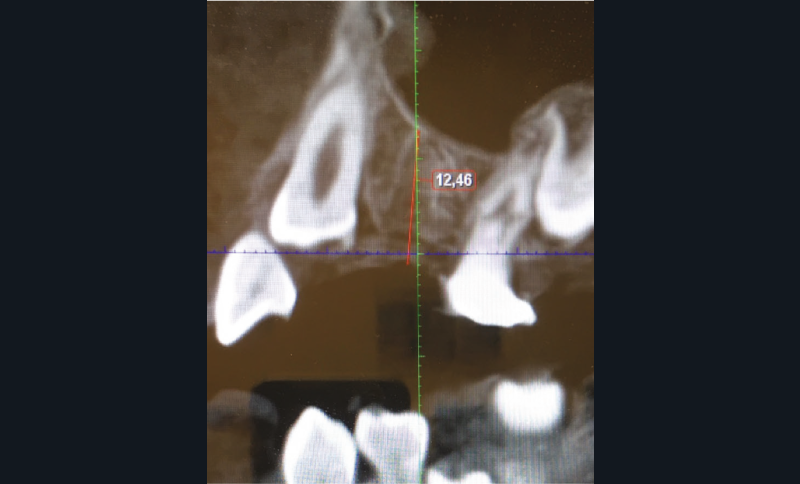

Un bilan radiologique 3D (Cone Beam CT) est prescrit dans le but d’évaluer, avec l’équipe de chirurgie du Dr Jean-Luc Charrier (Hôpital Bretonneau), la possibilité de transplantation d’une prémolaire du secteur 4 vers le secteur 1 et de définir le meilleur transplant possible entre 44 et 45. Sont analysées les dimensions du site receveur ainsi que l’anatomie, la position et l’état de maturation radiculaire des prémolaires candidates à la transplantation (fig. 3).

Cet examen nous apprend que :

- concernant le site receveur : son volume osseux est suffisant pour accueillir une des prémolaires du secteur 4 ;

- Concernant 45 :

- sa situation endo-osseuse (à l’abri de la flore bactérienne buccale et avec un desmodonte immature car non soumis aux stimuli occlusaux, facilitant une avulsion atraumatique) et son immaturité radiculaire franche (apex largement ouvert favorisant la revascularisation) font d’elle un transplant de choix ;

- mais il existe une proximité nette entre la couronne de 45 et la racine de 44, (augmentant le risque de lésion de 44 lors de l’avulsion de 45), et un rapport étroit entre la couronne de 45 et la corticale osseuse vestibulaire (augmentant le risque de lésion parodontale post-extractionnelle) ;

- enfin, 45 présente une longueur radiculaire encore courte risquant d’amener à un rapport couronne/racine limite in fine si l’édification radiculaire devait être stoppée après la transplantation de cette dent ;